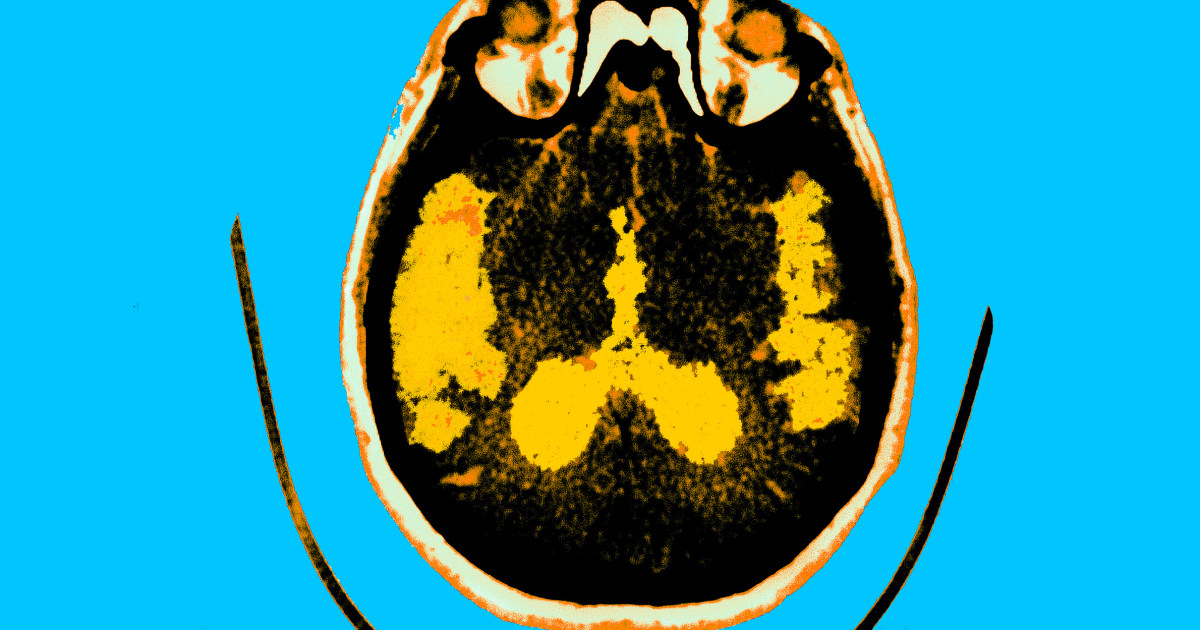

All three drugs are monoclonal antibodies that act against brain amyloid, which is considered a hallmark of Alzheimer’s disease.

Although the drugs appear to slow the disease in clinical trials, they have been hampered by concerns about potentially fatal side effects, such as brain inflammation and brain hemorrhages.